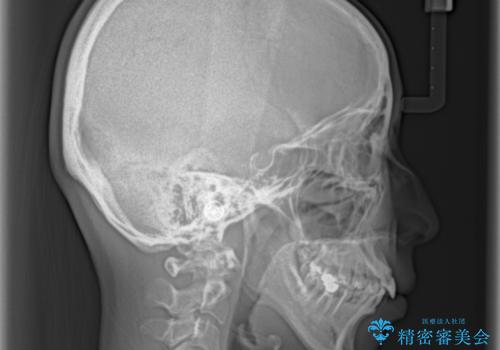

- 口元の閉じにくさと、奥歯の咬み合わせを気にして来院された患者様です。

左下の大臼歯2本が顕著に舌側に傾斜しているため、まずは奥歯の咬み合わせを改善をし、その後上下左右の第1小臼歯4本を抜歯することで口元を引っ込めながら整えることとしました。